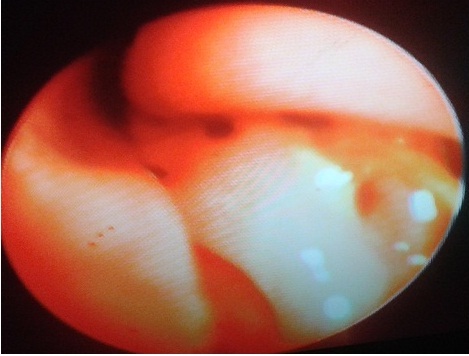

Toklász kutya orrüregében